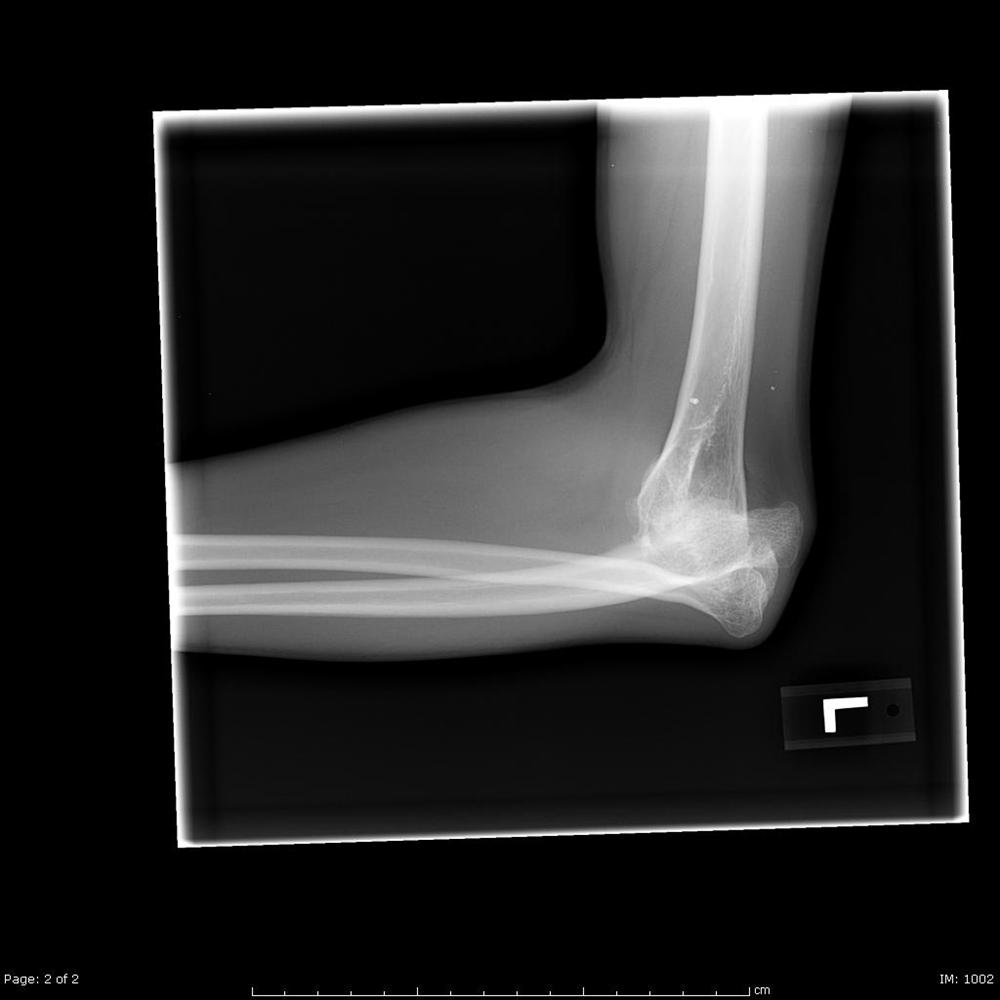

Elbow Dislocation Trauma Orthobullets Elbow Flexion Orthobullets Web place elbow in same position as the milking maneuver and apply a valgus stress while the elbow is ranged through the. Web if medial snapping only occurs during repeated or loaded extension/flexion of the elbow (in sports or work) it may be. The shaft for humerus has a spiral groove posteriorly (contains radial nerve) this lies approximately 13 cm. Elbow Flexion Orthobullets.

Elbow Dislocation Trauma Orthobullets Elbow Flexion Orthobullets The shaft for humerus has a spiral groove posteriorly (contains radial nerve) this lies approximately 13 cm proximal to the. Web acute medial elbow instability is usually a distinct and obvious diagnosis, but progressive attenuation and failure can be a gradual. Web patients are able to perform activities of daily living if elbow rom of 30 (extension) to 130 (flexion). Elbow Flexion Orthobullets.

Elbow Dislocation Pediatric Pediatrics Orthobullets Elbow Flexion Orthobullets ( i ) quantitative anatomic dissection and description of the medial and lateral. Web acute medial elbow instability is usually a distinct and obvious diagnosis, but progressive attenuation and failure can be a gradual. Web place elbow in same position as the milking maneuver and apply a valgus stress while the elbow is ranged through the. Web if medial snapping. Elbow Flexion Orthobullets.